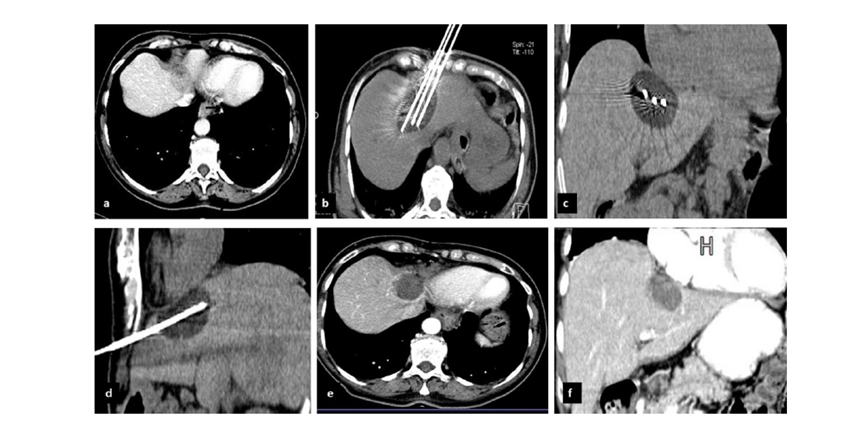

冷冻消融胆囊附近肿瘤病灶

(A)动脉期 MRI 显示胆囊附近有外周增强病变(箭头)。

(B)手术过程中 CT 显示冷冻探针位于病灶内。

(C)消融后,术后 1 个月CT 显示完全消融(箭头)。

(A)动脉期CT图像显示有一个包膜下结节(箭头)。(C) 在手术过程中的CT显示一个冷冻探针位于病灶内。随访时间中位数为7个月(范围:3-12个月),随访期间患者无局部肿瘤进展或死亡。

(A)门静脉期 CT 图像显示胆囊附近有病变(箭头)。(D)消融手术后 1 个月CT 显示完全消融。

CT引导的冷冻消融